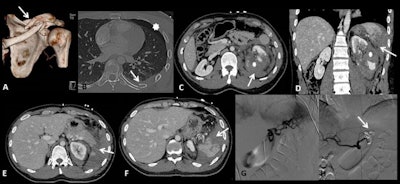

Angiography with embolization has a pivotal role in the treatment of vascular and parenchymal injuries, they pointed out. "Radiography is the first-line tool in the evaluation of a bony injury of the upper and lower extremities. Ultrasound still has an important role in minor blunt abdominal trauma, particularly in the pediatric population due to the absence of ionizing radiation."

Direct impact due to collision with stationary objects (such as trees or rocks, other bikers, or unexpected hikers on the trails) or with the handlebars may result in a blunt trauma that most commonly involves solid organs of the abdomen.